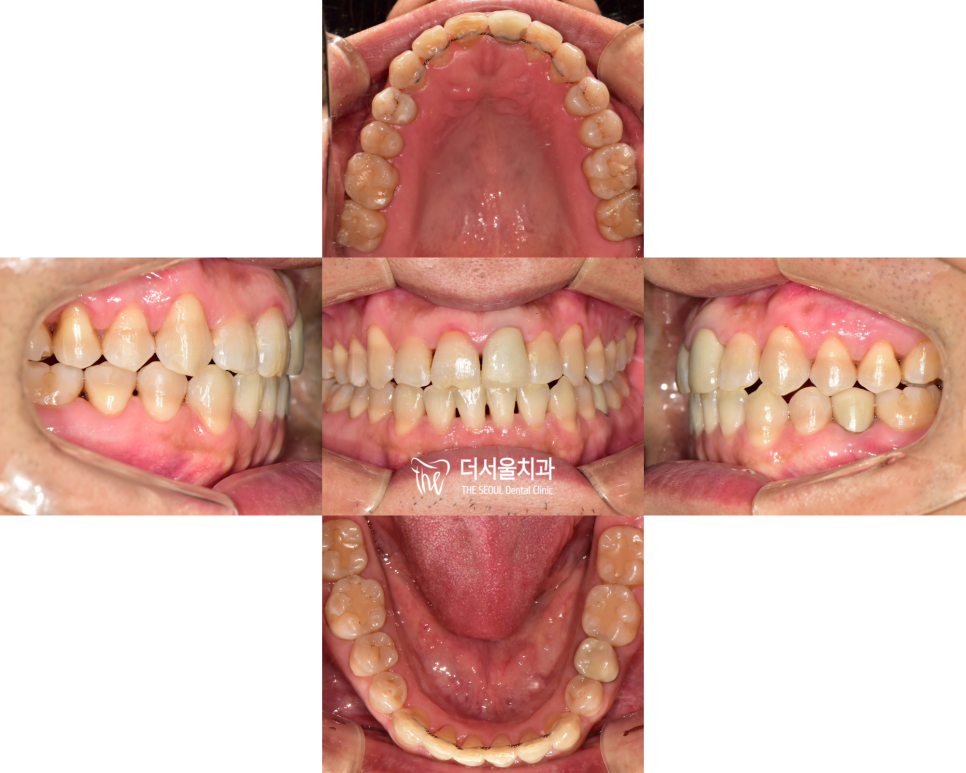

고난도 인비절라인 과정이

드디어 마무리 되었습니다.

훨씬 안정적인 모습을 갖게 되었으며

반대교합 및 주걱턱 경향이 개선되었는데요.

이전에 비해 고르게 바뀐 모습을

확인할 수 있네요^^

비수술이라 안모의 큰 변화는 없지만

입매가 세련되게 변한 것을 볼 수 있습니다.

치료기간 2019.04.24 ~ 2021.05.06